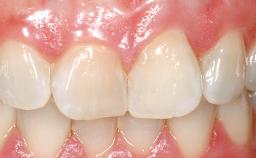

A 30-year-old female patient was referred to the office for the treatment of tooth 11. Her chief concern at the initial visit was to inquire, “Why is my tooth pink?” Upon clinical examination, it was determined that tooth 11 had a previous history of trauma and that the clinical crown had become noticeably pink in color as a result of internal resorption. This diagnosis was confirmed radiographically, indicating a large radiolucency involving the central and distal portions of the clinical crown. It was determined that restoration of this tooth was not possible, and that extraction was indicated. The presence of a mid-line diastema, which the patient wanted to reproduce, directed the treatment plan for tooth replacement utilizing a dental implant.

Prosthesis Type FDP

SAC Level Advanced

Defining Characteristics One missing tooth to be replaced by an implant-borne crown

Esthetic Risk High